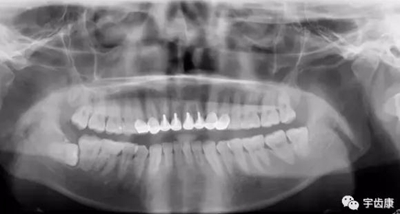

X線閱片知識(shí)